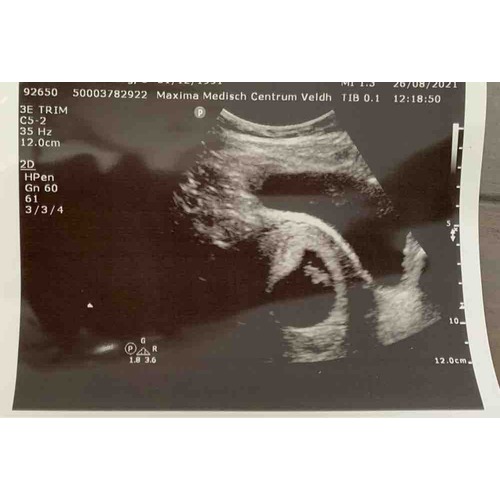

Mijn echo van 8+5! Vrijdag mag ik terug dan ben ik 10+2